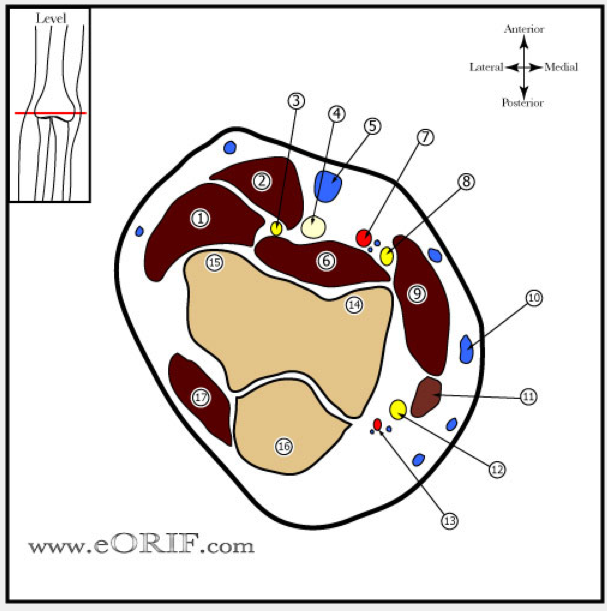

NAME THE ANATOMICAL STRUCTURES

Course of the radial nerve, hitting salient points

From posterior cord

Travels in poseterior aspect of axilla

Through triangular interval with profunda brachii artery

In the spiral groove 14-15cm proximal to lateral epicondyle

Exit the lateral intermuscular septum never less than 7.5cm from distal articular surface

Travels between brachialis & brachioradialis anterior to lateral epicondyle

Divides into SRN and PIN at level of radiocapitellar joint